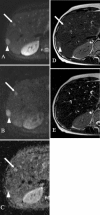

Methods: Seventy-three patients with 215 confirmed FLLs (115 benign, 100 malignant) underwent 1.5-T MRI with respiratory-triggered single-shot SE DWI (b = 50, 400, 800) and dual-echo T2TSE (TR = 3,000 ms; TE1 = 84 ms; TE2 = 228 ms). ADC values and T2 relaxation times of FLLs were calculated. Sensitivity, specificity and accuracy of both techniques in diagnosing malignancy were assessed.

Results: The mean ADC value of malignant tumours (1.07 × 10(-3) mm(2)/s) was significantly lower (P < 0.05) than that of benign lesions (1.86 × 10(-3) mm(2)/s ); however, with the use of the optimal cut-off value of 1.25 × 10(-3) mm(2)/s, 20 false positive (FP) and 20 false negative (FN) diagnoses of malignancy were noted, generating 79 % sensitivity, 82.6 % specificity and 80.9 % accuracy. The mean T2 relaxation time of malignant tumours (64.4 ms) was significantly lower (P < 0.05) than that of benign lesions (476.1 ms). At the threshold of 107 ms 22 FP and 1 FN diagnoses were noted; the sensitivity was 99 %, specificity 80.9 % and accuracy 89.3 %.